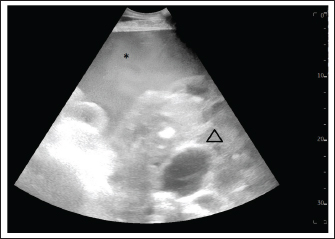

During the following 3 days, the hemoperitoneum regressed and the mare no longer showed signs of abdominal discomfort. Ultrasonographically, a mass with a honeycomb structure was visible bilaterally in the inguinal region of the abdomen (Fig. 2). The firm structure that was palpable transrectally was unchanged, and transrectal ultrasonography revealed that it was the same mass as seen inguinally. Differential diagnoses included a GCT, GTCT, and hemangiosarcoma. Since the owner declined laparoscopy and biopsy, the blood concentration of anti-Mullerian hormone was determined and was highly suggestive of a GCT (22.96 ng/ml; reference interval for healthy mares <4 ng/ml, equivocal 4–7 ng/ml, suggestive of GCT >7 ng/ml). The mare was discharged from the hospital 14 days after the initial presentation since the owners initially declined further treatment due to a guarded prognosis and financial limitations. At the time of hospital discharge, the mare was clinically stable, and the anemia had improved (PCV 29%, reference interval 27%–39%, RBC 5.91 T/l, reference interval 6.6–9.8 T/l, hemoglobin 6.3 mmol/l, reference interval 7.2–10.2 mmol/l) and the amount of intra-abdominal free fluid had significantly decreased.

Fig. 2. Ultrasound examination of the abdomen on admission, one month after initial discharge. The image was acquired in the left inguinal region. The hemoperitoneum had completely resolved. The hemorrhage caused severe subcutaneous oedema (*). The honeycomb structure is visible (triangle) and has not increased in size. Without hemoperitoneum, it was easier to follow the shape of the GCT, excluding interaction with other organs.